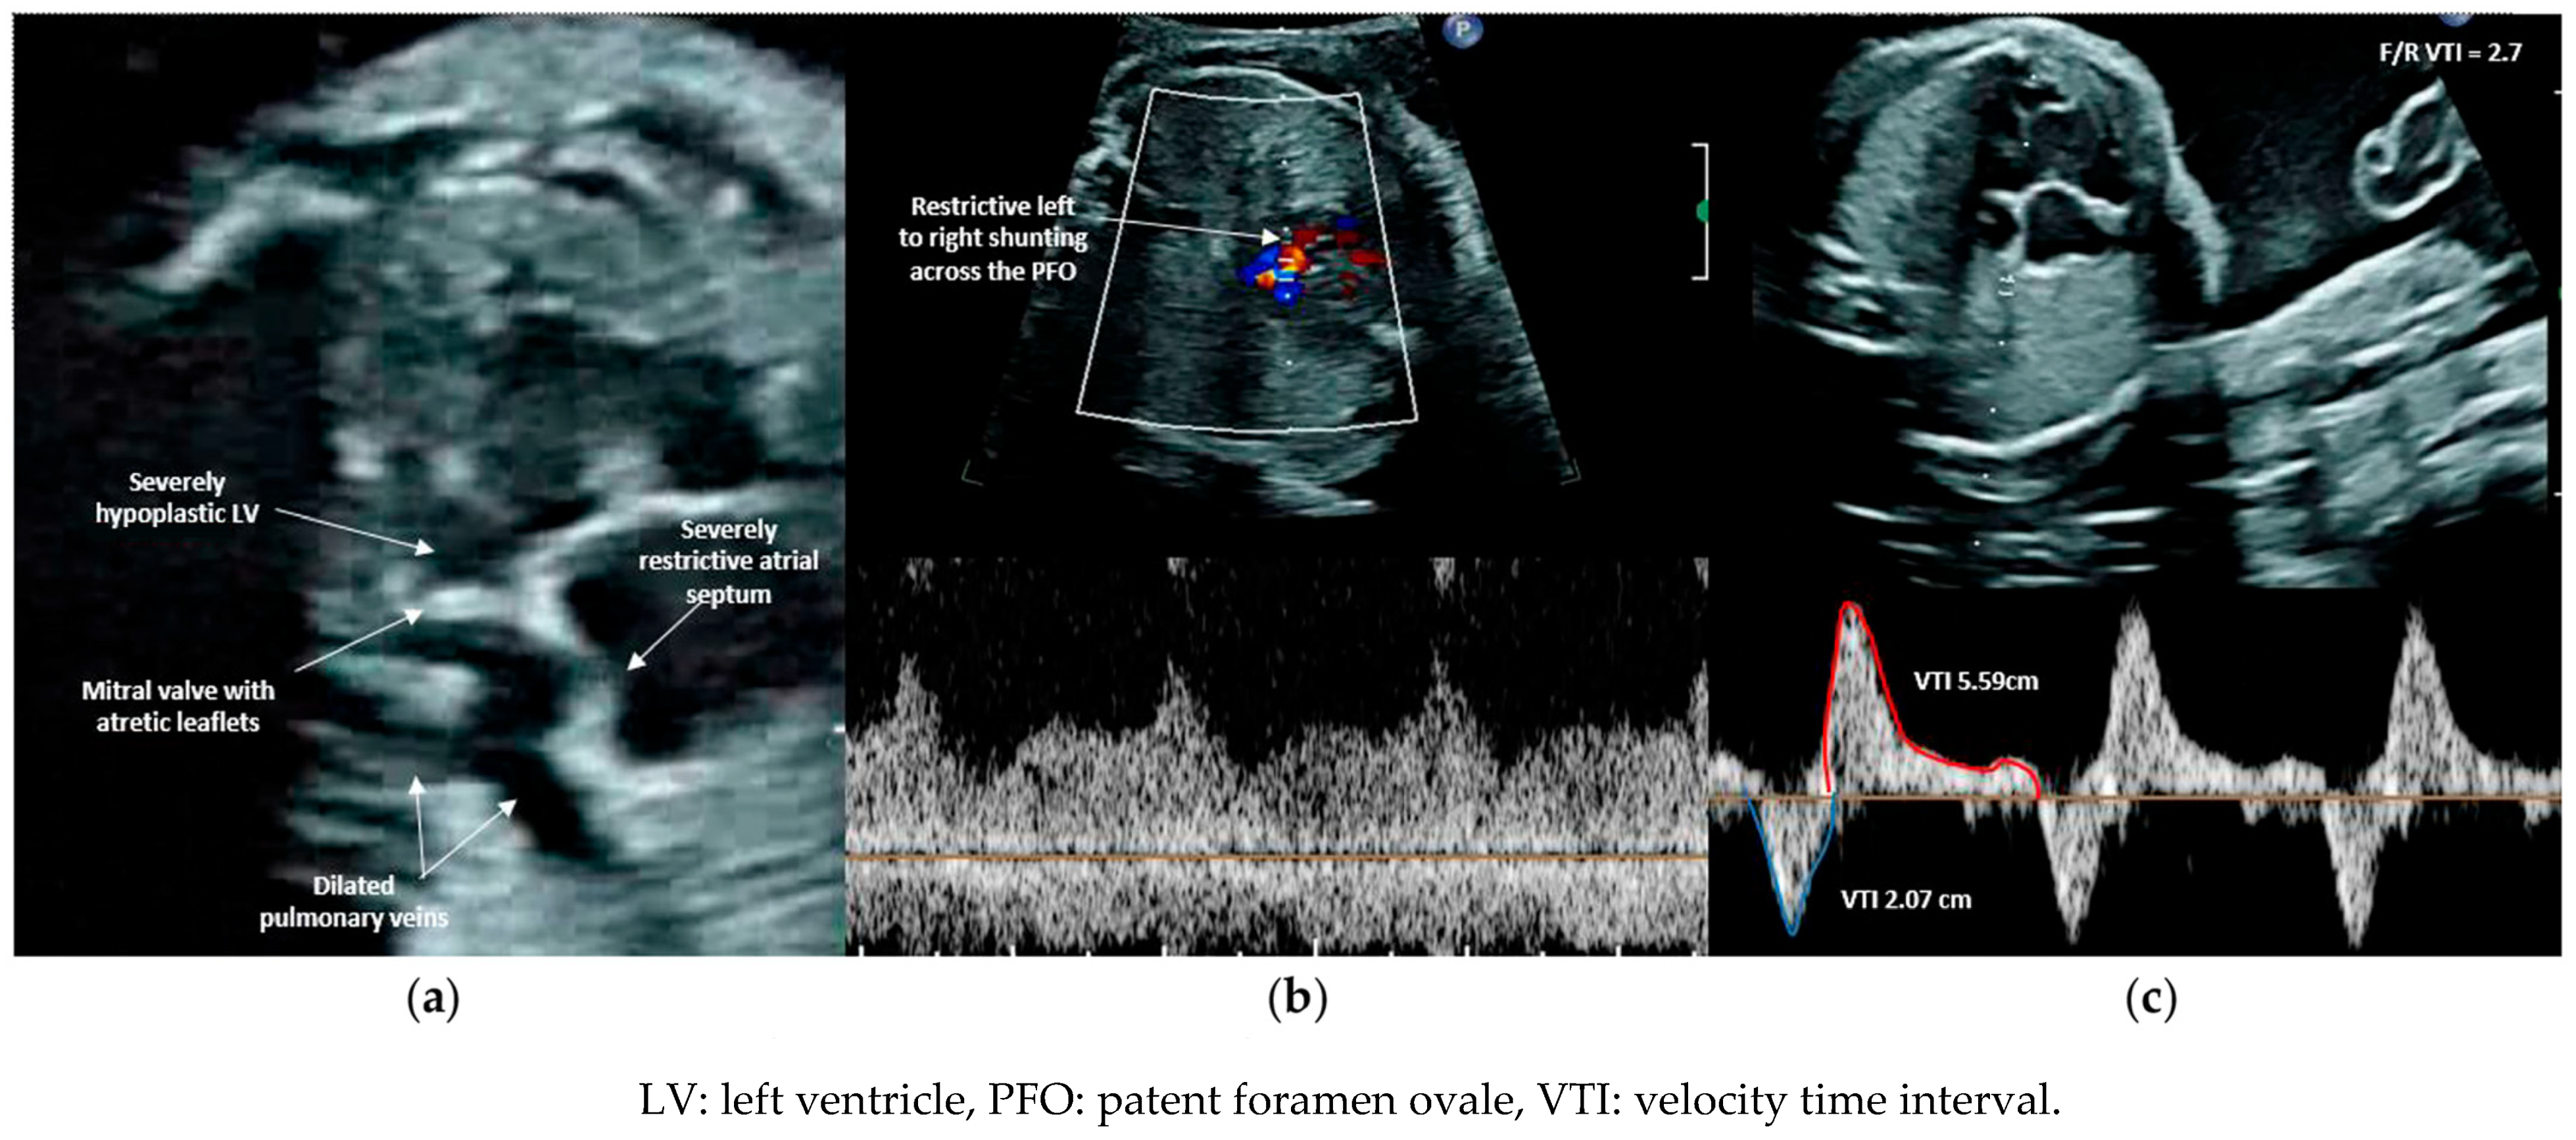

3.1. Patient Selection

3.2. Procedural Technique